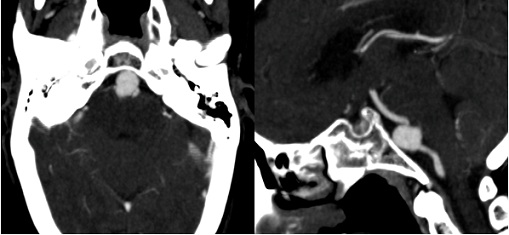

CT revealed a large saccular aneurysm of 13 x 16 mm, with a wide neck (05 mm), implanted on an asymmetric fenestration of the vertebrobasilar junction, without any sign of complication (Figures 1-3).

Figure 1: Cerebral CT angiography. A) Oblique axial section and sagittal reconstruction; B) Show a large unruptured saccular aneurysm (blue arrows) on the proximal portion of the basilar trunk (red arrow).